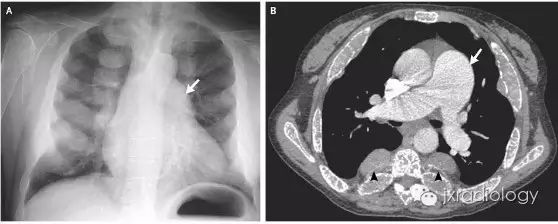

髓外造血器官,影像学上通常表现为器官增大,如超声、CT或MRI上表现为肝肿大、脾大。然而,在不常见的情况下,髓外造血可以发生在胸腔内,呈后纵隔肿块,变现为单侧或双侧脊柱旁肿块,边缘光滑,轮廓分明,常呈分叶状边缘。

(图源:N Engl J Med 2010; 362:253)